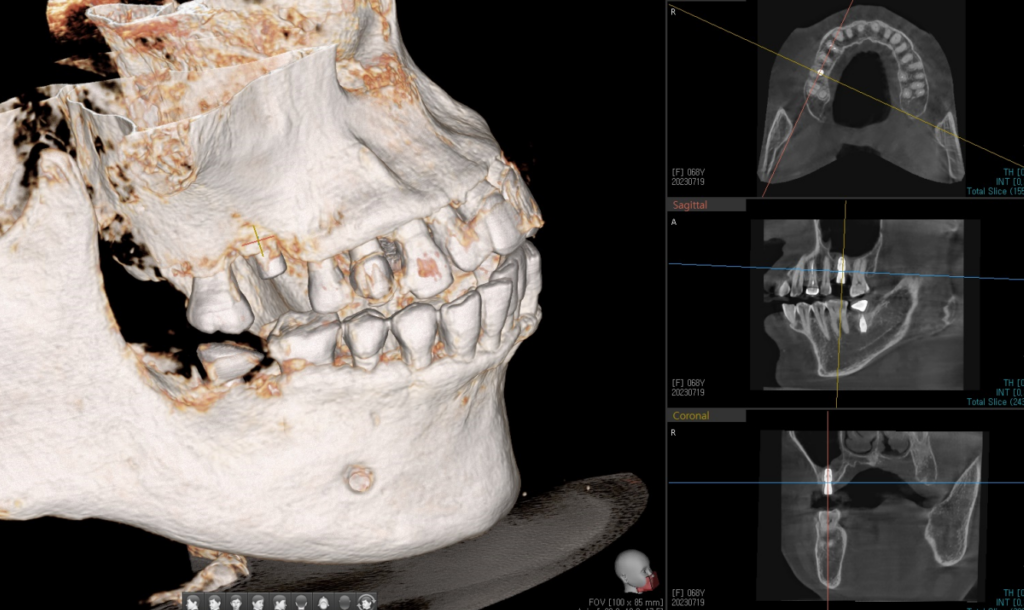

23. 02. 24(CT 상에서 발견되는 임플란트 주위염)

엑스레이와 같은 2D 영상에서는 보이지 않았던 임플란트 주변 뼈의 파괴가 CT에서는 3D 로 보기 때문에 확연하게 보입니다. 임플란트 뿌리 주위로 염증이 옮아 있었고 나사선을 타고 뿌리까지 내려가 치아의 흔들림을 만들어 낸 것입니다.